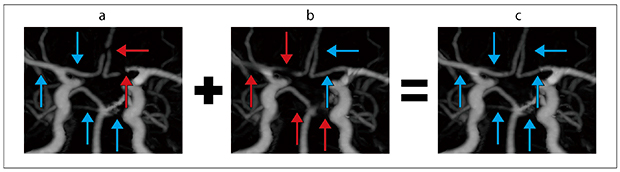

MIP画像のFBPでは前大脳動脈が描出不良である(図2 a)。O-MARでは右中大脳動脈・右前大脳動脈・左後大脳動脈・両側上小脳動脈が描出不良である(図2 b)。fusionではFBPとO-MARで描出不良な血管がすべて良好に描出されている(図2 c)。

図2 頭部3D-CTA MIP画像(→:描出良好,→:描出不良)

a:FBP。前大脳動脈に描出不良箇所を認める(←)。

b:O-MAR。右中大脳動脈・右前大脳動脈・左後大脳動脈・両側上小脳動脈に描出不良箇所を認める(↑)。

c:fusion。すべての血管描出が良好である(↑)。